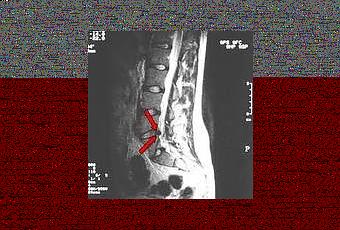

Las inyecciones con etanol gelificado mejoran la hiperpresión dentro del disco bajando la inflamación, produciendo una regeneración del disco tratado. La técnica ha comenzado a ser utilizada en la Clinica La sagrada Familia en Buenos Aires Argentina y en los últimos dos años, ya son 12 los pacientes tratados y hasta ahora, la evolución ha sido buena sin recidivas ni recurrencias. En los estudios de control realizados con estos pacientes se ve que el disco se retrajo satisfactoriamente y, sobre todo, se aprecia una mejoría clínica, que tarda entre 3 y 4 semanas, y culmina con la desaparición del dolor. Esta experiencia fue presentada en la SIMI-2010, que se realizó junto con el XXII Congreso de la Sociedad Ibero-Latinoamericana de Neurorradiología, Diagnóstico y Terapéutica (Silan). Su uso evita la cirugía abierta, en la que hay que cortar músculo, resecar un pedacito de la vértebra, para llegar al disco y extraerlo. Aquí, lo que se hace es inyectar una sustancia a base de alcohol gelificado y tungsteno, con el objetivo de terminar de deshidratar el fragmento del disco afectado, que una vez seco se retrae, vuelve a su lugar y deja de comprimir la raíz. Es una forma de reconstuir el disco sin perder la estabilidad de la columna y sin internación, ya que el tratamiento es ambulatorio.